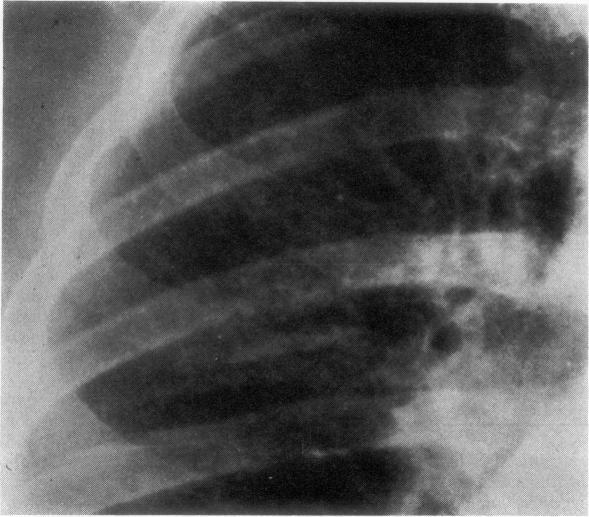

Right-heart overload happens relatively rarely in sarcoidosis, even with fibroemphysematous changes. Of 21 cases that we studied, six (28%) had clinical and/or electrocardiographic features of cor pulmonale. The cause of cor pulmonale often evoked is an invasion of the walls of pulmonary vessels by sarcoid granulomas or their compression by the fibrotic process. Pathological studies in one patient showed compression of large pulmonary arteries associated with specific sarcoid lesions in small small and medium-sized arteries.

即使存在纤维性肺气肿改变,结节病中右心负荷过重相对少见。在我们研究的21例病例中,6例(28%)有肺心病的临床和/或心电图特征。常被提及的肺心病病因是结节病肉芽肿侵犯肺血管壁或纤维化过程对其造成压迫。对1例患者的病理研究显示,大肺动脉受压,同时在中小动脉存在特异性结节病病变。